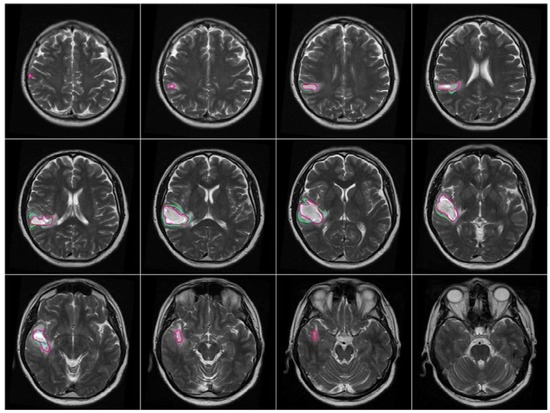

After the brain tumor location was recognized and identified by BBBDG, the 3DACWE approach was initialized and applied to the T2-w MRI brain scan images of 12 MRI slices from the collected dataset (Figure 9). The ground truth provided by the clinician are marked in green, and the tumor boundaries extracted by 3DACWE are marked in red. This patient holds a brain tumor in the left brain hemisphere. The 3DACWE was initialized by the following initial parameters: λ1 = λ2 = 1 and length penalty μ = 106.

Figure 9. Comparative segmentation results on MRI T2-w (normalized) scan (matching images in Figure 7) by 3DACWE. The ground truth is marked in green, and the output of 3DACWE is marked in red.